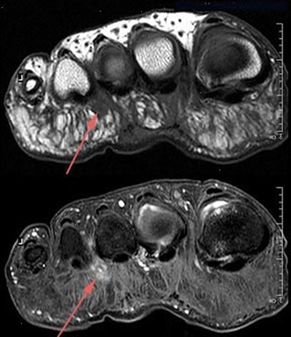

La diagnosi viene confermata (oltre che dai sintomi e i test sopra descritti) anche dall’ecografia, ed eventualmente dalla RNM.